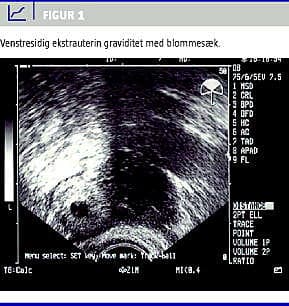

En 33-årig kvinde blev henvist til Gynækologisk Afdeling med nedre abdominalsmerter. Tidligere gynækologisk rask, en provokeret abort for otte år siden, en normal fødsel for tre år siden. Nu spontant gravid med menostasi svarende til uge 6+4. Hun havde gennem nogle dage haft intermitterende venstresidige nedre abdominalsmerter, som nu var tiltaget, og der var forværring ved bevægelse. Der var sparsom vaginalblødning. Objektivt var patienten upåvirket, ved gynækologisk undersøgelse fandtes ømhed og peritonealreaktion over venstre adnex. Ved vaginal ultralydskanning fandtes en venstresidig ekstrauterin gestationssæk med en blommesæk (Figur 1 ) og desuden en moderat mængde fri væske i abdomen. Højre adnex var upåfaldende, og uterus var tom med normalt endometrium.